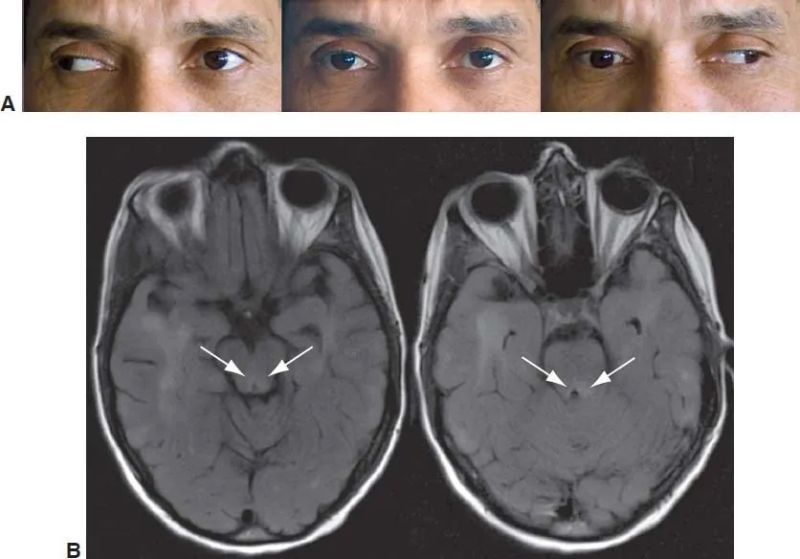

Bilateral internuclear ophthalmoplegia in a 53-year-old man with diplopia on lateral gazes. A, Horizontal gaze in either direction results in full abduction of the ipsilateral eye but virtually no adduction of the contralateral eye. Alignment in primary gaze (center panel) is nearly orthotropic. B, Axial FLAIR MRI brain scan showing edema (bright signal indicated by arrows) in the area of the medial longitudinal fasciculus bilaterally at the level of the upper midbrain (left) and pons (right). (Courtesy of Prem S. Subramanian, MD, PhD.)

Bilateral internuclear ophthalmoplegia. American Academy of Ophthalmology. https://www.aao.org/education/image/bilateral-internuclear-ophthalmoplegia Accessed October 1, 2024.